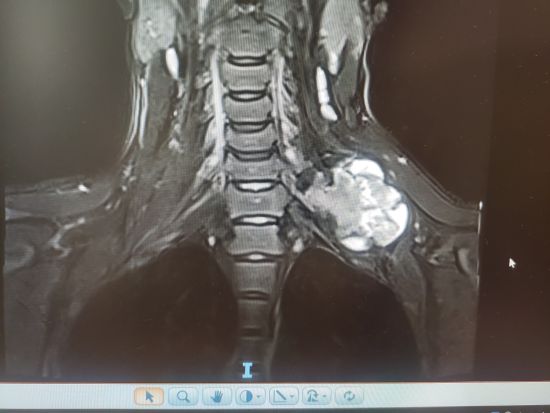

经详尽的影像学检查,小木被诊断为颈肋软骨瘤。这一发现令全家震惊不已,他们感到前所未有的压力。骨科主任杜东鹏详细介绍了小木的病情:“这个肿块直径约7厘米,质地坚硬,固定于第7颈椎的横突部位。”他指出,其颈肋就是一个比较少见的发育畸形,而在颈肋上长出软骨瘤就更加少见,尤其是软骨瘤长在颈椎旁狭小空间,这给手术治疗带来了很大风险和挑战。

为降低手术风险,杜主任团队进行了充分的术前准备,实施了介入治疗以缩小肿瘤软组织体积。手术当天,先切除锁骨,在显微镜下小心翼翼地进行左颈部肿物切除术及左侧锁骨截骨内固定术。经过2个多小时的紧张操作,最终成功将大小约12厘米×7厘米×5厘米的肿瘤完整取出。“整个过程我们都非常小心,确保不伤及周围的血管和神经。”杜主任回忆道,“最终手术非常成功,肿瘤完整取出,且没有出现任何并发症。”